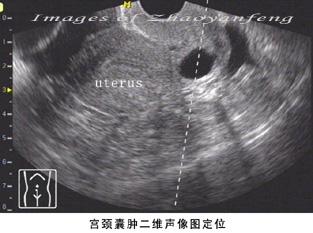

三、宫颈囊肿的图片:

宫颈囊肿的B超图片